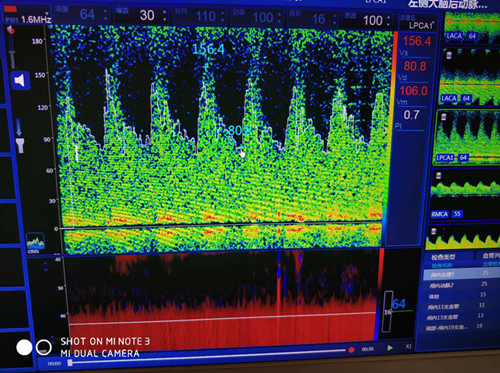

大腦后動脈血流速度增高